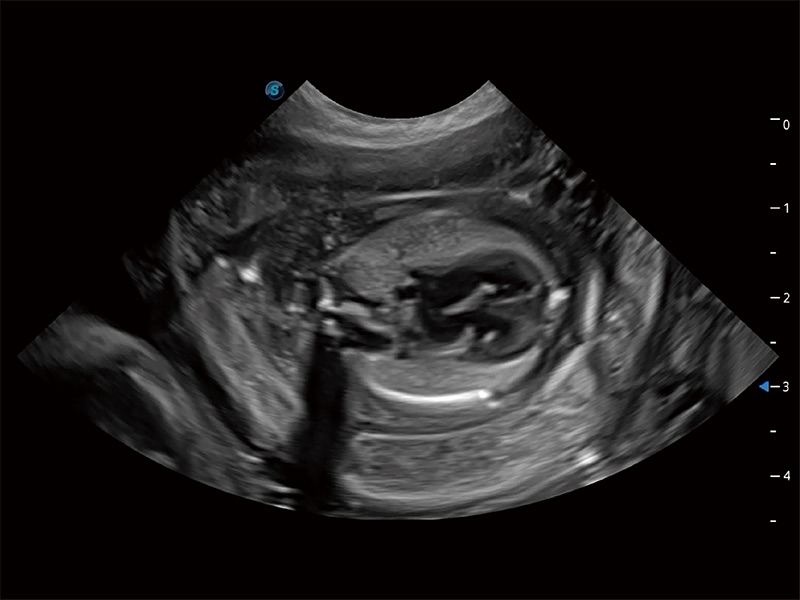

高性能和先進(jìn)的臨床應(yīng)用工具可以為動(dòng)物醫(yī)生提供臨床信心。ProPet 80 搭載了先進(jìn)的腹部和淺表應(yīng)用工具,幫助醫(yī)生在日常臨床實(shí)踐中發(fā)揮前所未有的作用。

ProPet 80 專為動(dòng)物醫(yī)生設(shè)計(jì),對(duì)不同的動(dòng)物體型和生理結(jié)構(gòu)作出了針對(duì)性的優(yōu)化。通過動(dòng)物影像專用軟件,可滿足個(gè)性化的應(yīng)用需求,幫助動(dòng)物醫(yī)生獲得更精確的診斷數(shù)據(jù)。

ProPet 80 全新的動(dòng)物超聲智能軟件和豐富的探頭群,為動(dòng)物醫(yī)生提供了高清晰度和精細(xì)分辨率的圖像,無論在寵物、馬科、畜牧還是實(shí)驗(yàn)室動(dòng)物等應(yīng)用中都可以輕松應(yīng)對(duì),為您的日常工作帶來滿意的體驗(yàn)。